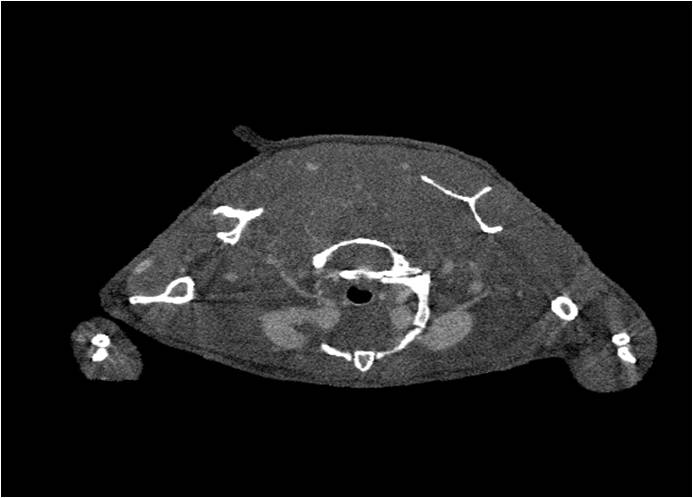

小鼠股骨

超高分辨率模式下像素大小為9μm。

A軸向和矢狀面顯示小鼠股骨結構。

B用鈦材料植入的穿過骨頭的冠狀切片